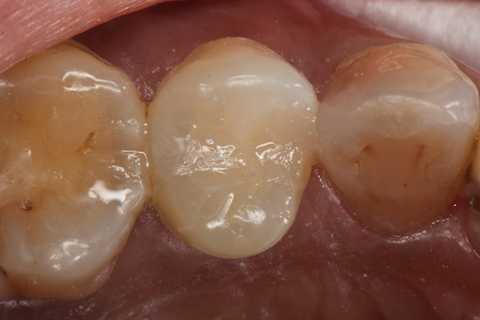

40代女性、左上5、冷水痛+

注意点はCRの接着面は新鮮歯質を確保して歯髄に近いところの軟化象牙質はあまり追求しないでも良い。α-TCPセメントの硬化と接着を妨げない程度に乾燥できれば良い。軟化象牙質は原材料のα-TCPと多少の水分があれば自然に再硬化するようだ。

この症例はストリップスを使っていない。使わない方が確実に充填できると思う。

では時系列でどうぞ